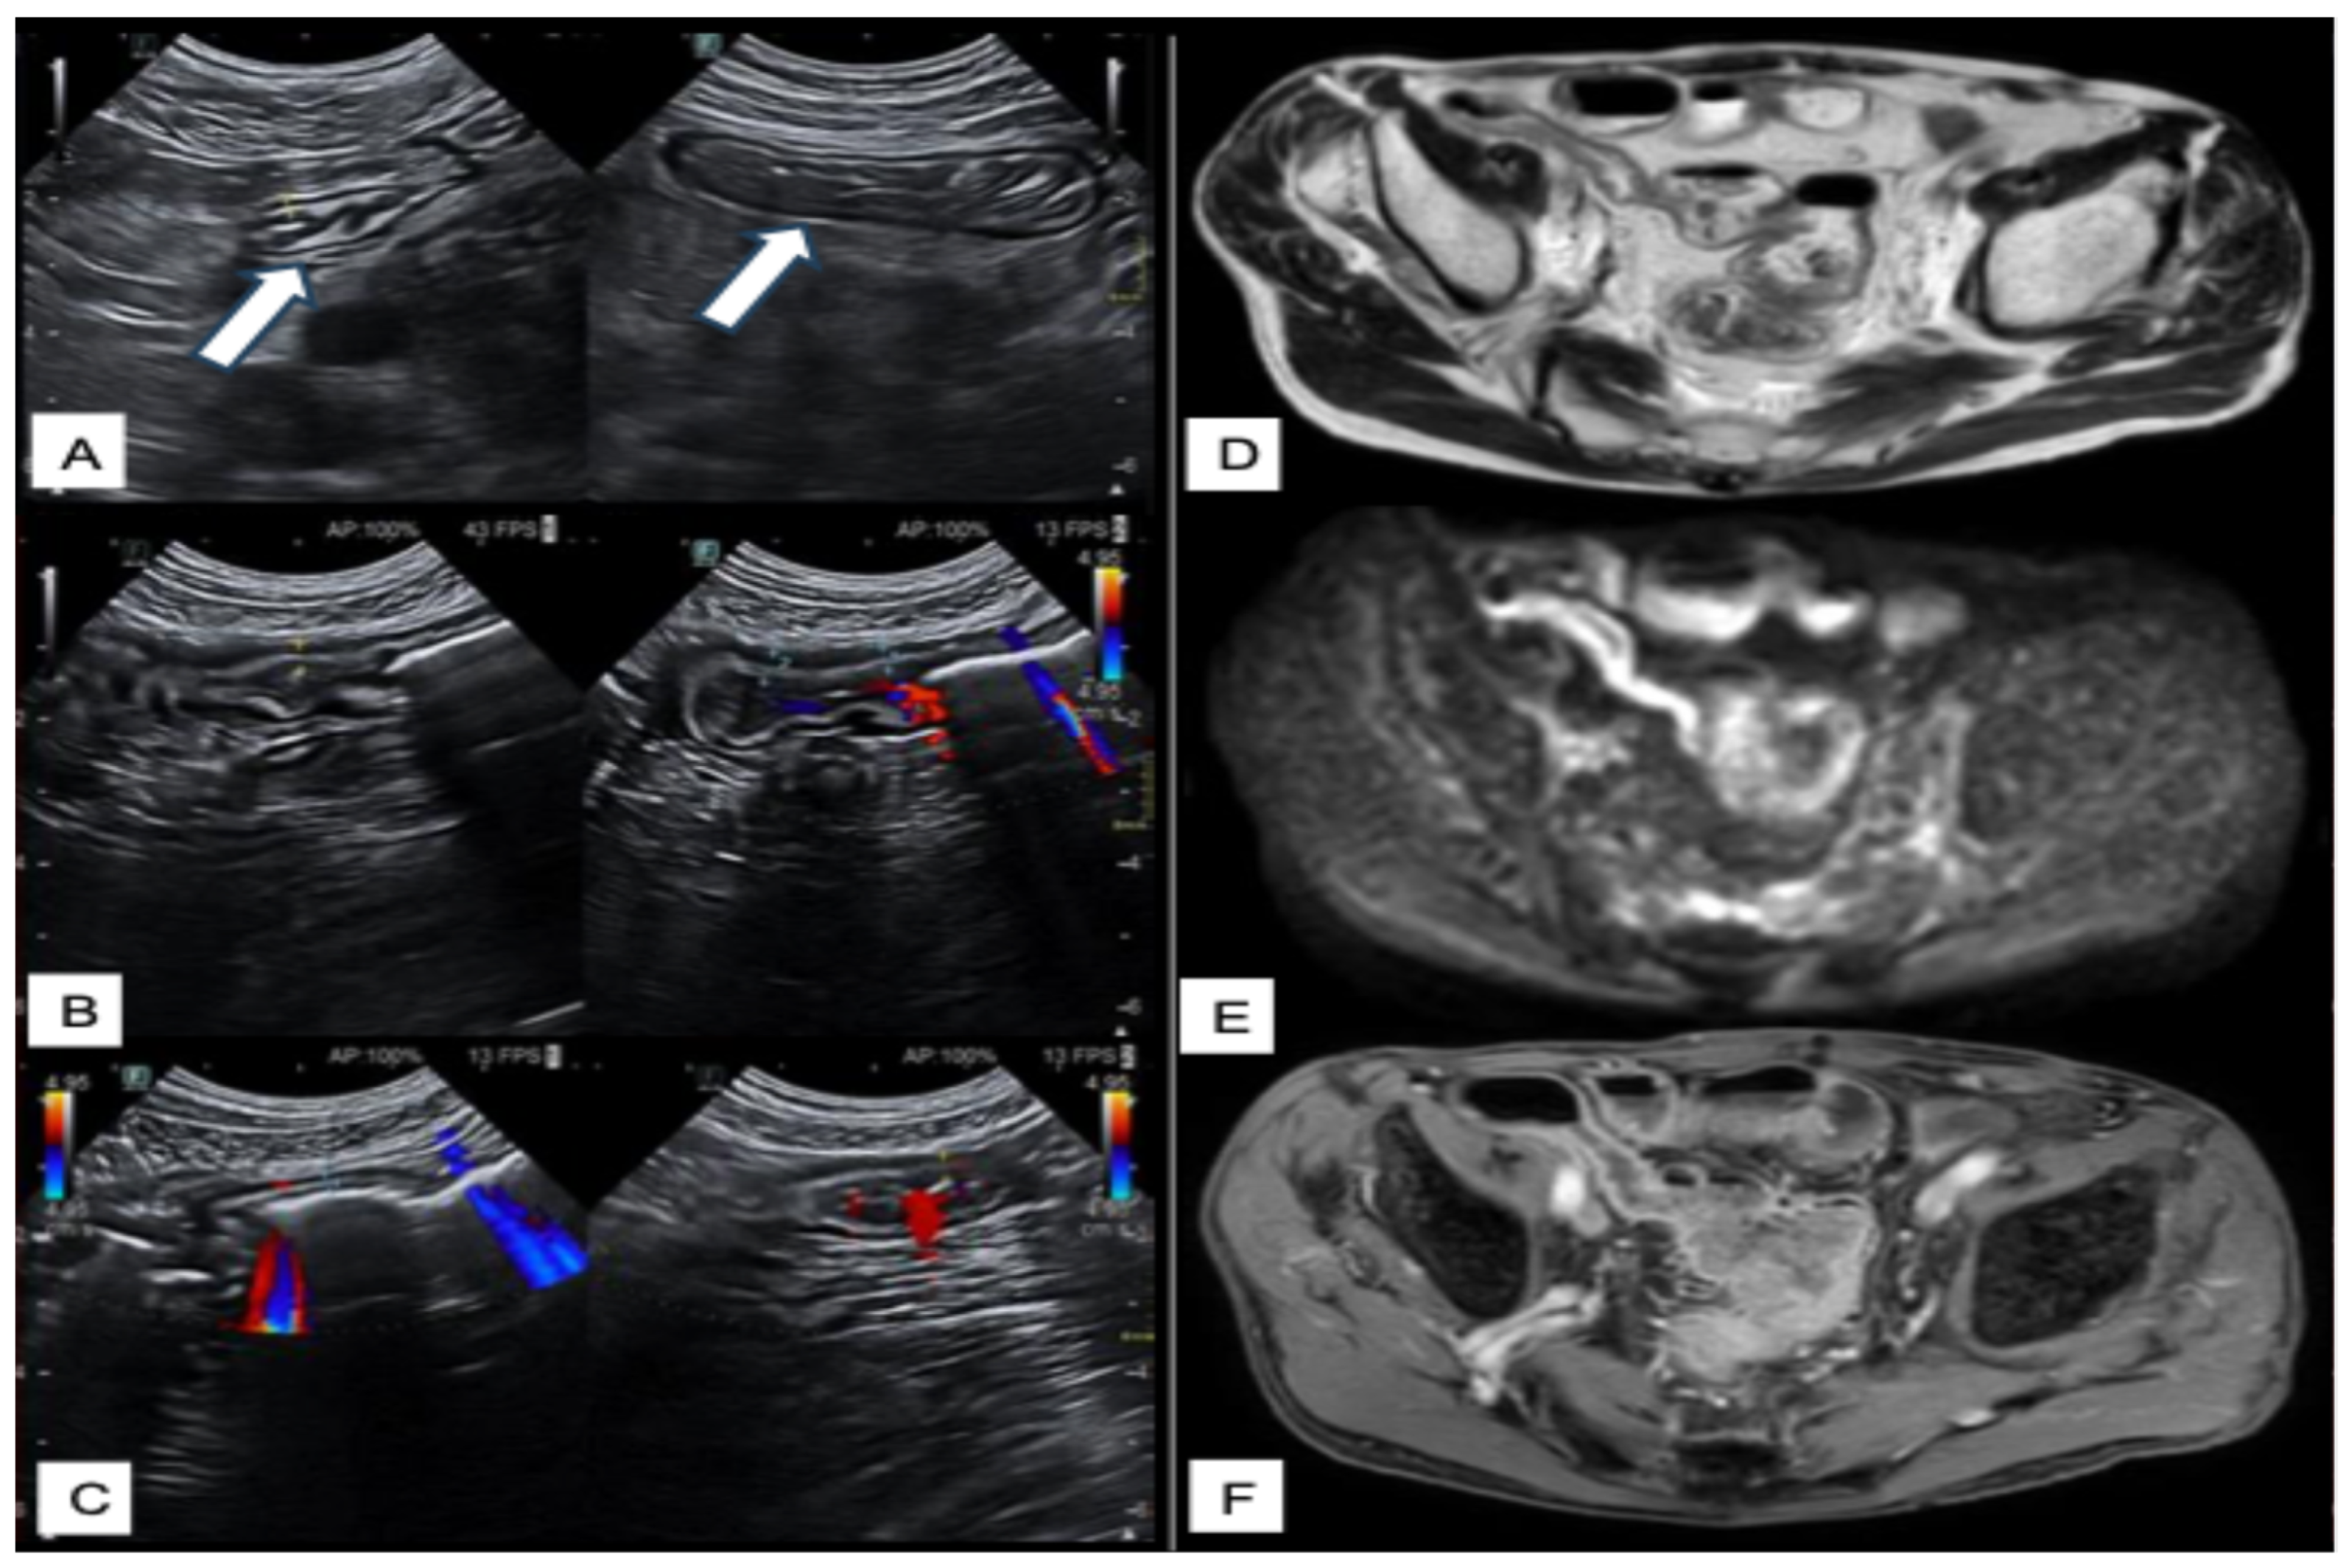

Intestinal Ultrasounds Imaging Findings and Scoring Systems

- Celikyay, F.; Yuksekkaya, R.; Yuksekkaya, M.; Kefeli, A. Color Doppler Ultrasound Assessment of Clinical Activity in Inflammatory Bowel Disease. Curr. Med. Imaging 2021, 17, 741–750. [Google Scholar] [CrossRef]

- Ripollés, T.; Martínez-Pérez, M.J.; Blanc, E.; Delgado, F.; Vizuete, J.; Paredes, J.M.; Vilar, J. Contrast-enhanced ultrasound (CEUS) in Crohn’s disease: Technique, image interpretation and clinical applications. Insights Imaging 2011, 2, 639–652. [Google Scholar] [CrossRef]

- Gallego, J.C.; Echarri, A. Role of magnetic resonance imaging in the management of perianal Crohn’s disease. Insights Imaging 2018, 9, 47–58. [Google Scholar] [CrossRef]

- Gage, K.L.; Deshmukh, S.; Macura, K.J.; Kamel, I.R.; Zaheer, A. MRI of perianal fistulas: Bridging the radiological-surgical divide. Abdom. Imaging 2013, 38, 1033–1042. [Google Scholar] [CrossRef]